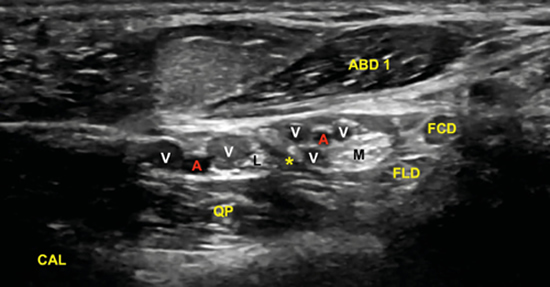

No obstante, la visualización de los nervios plantar medial y plantar lateral es más evidente cuando se avanza hacia distal. Para ello se mantiene la sonda en eje corto (Figura 13) tomando como referencia la tuberosidad posterior del calcáneo, de donde parten el eje de Dellon-Mackinnon4 y el triángulo de Heimkes (área entre tuberosidad del calcáneo, el vértice del maléolo medial y el navicular)8 (Figura 12).

La imagen sonográfica se centrará en el espacio situado bajo la fascia profunda del músculo abductor del primer dedo, por donde discurrirán los haces neurovasculares plantar medial y plantar lateral, diferenciados y separados por el septo de Heimkes o interfascicular3. El nervio plantar medial se muestra con mayor sección que el nervio plantar lateral, y las venas laterales con mayor luz que las mediales (Figura 14).

Figura 14. El septo interfascicular (*) parte desde la fascia profunda del músculo abductor del primer dedo (ABD 1) hacia el tendón flexor largo del primer dedo (FLD) dividiendo la cámara superior de la cámara inferior, donde respectivamente se encuentran el haz neurovascular plantar medial (M: nervio plantar medial; A/V: arteria y venas plantar medial) y el haz neurovascular plantar lateral (L: nervio plantar lateral, A/V: arteria y venas plantar lateral). En profundidad, el músculo cuadrado plantar (QP) y la superficie del calcáneo (CAL).